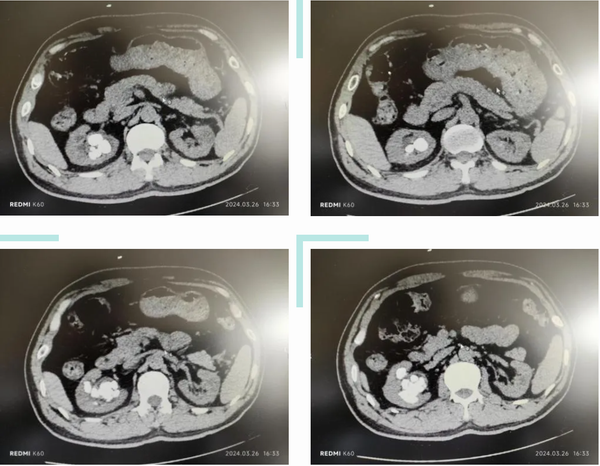

病例:王先生因右側(cè)腰腹部疼痛發(fā)現(xiàn)右腎多發(fā)結(jié)石,較大的直徑約2.1cm。其所居住的當(dāng)?shù)蒯t(yī)院提出多次手術(shù)治療結(jié)石的方案,王先生不愿承受多次手術(shù)的痛苦,慕名來到玉溪市中醫(yī)醫(yī)院外二科(泌尿外科、男性科)就診。

術(shù)前結(jié)石CT影像

接診的外二科副主任醫(yī)師李家平詳細(xì)詢問病史,仔細(xì)查體閱片,最終決定采用目前最先進(jìn)的第五代EMS碎石系統(tǒng),為王先生實(shí)施經(jīng)皮腎鏡氣壓彈道聯(lián)合超聲碎石清石術(shù)。一次手術(shù)便成功擊碎并吸出王先生右腎內(nèi)多發(fā)結(jié)石,術(shù)后恢復(fù)良好。復(fù)查KUB顯示其右腎內(nèi)已無結(jié)石殘留,術(shù)后僅在腰部留有一個長約1cm的疤痕。